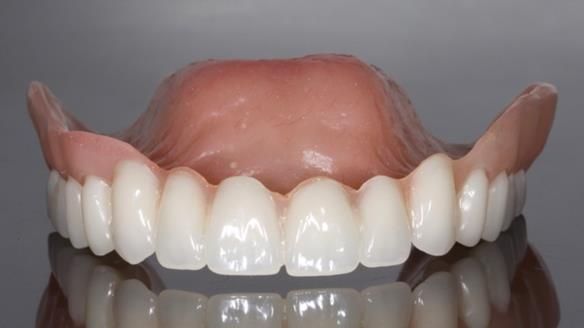

In this edition, I present the complete denture treatment for Kate, a 69-year-old American woman living in Garstang, UK. Kate had been edentulous for many years and required a set of complete dentures that closely mimicked her natural teeth. The new upper and lower dentures provided excellent retention and stability, with significant suction in the upper denture. Below, I detail the step-by-step process of her treatment, as well as my workflow for implant-supported overdentures for patients who may require them.

Kate had previously undergone treatment for Stage T3 breast cancer, which included three rounds of six-monthly bisphosphonate IV infusions. As a result, dental implants were not a viable option due to the high risk of MRONJ (medication-related osteonecrosis of the jaw), despite Kate having saved up money for implant-supported teeth. She was referred to me to deliver technically excellent dentures. Interestingly this case on my teaching website attracted her to the practice.

The treatment was a resounding success, meeting all of Kate’s expectations. While I was confident I could achieve a natural appearance, the challenges of gagging, denture stability, and eating were less predictable and uncertain. I discussed these concerns thoroughly at the outset, and Kate decided to proceed despite the high cost. She expressed that there was no pressure to move forward with the treatment, and she’s been delighted with the life-changing results.

Treatment Process: I provided the clinical work while Rowan Garstang and Sam Hesketh delivered the technical aspects. The treatment required fifteen visits to fit and review Edgar.